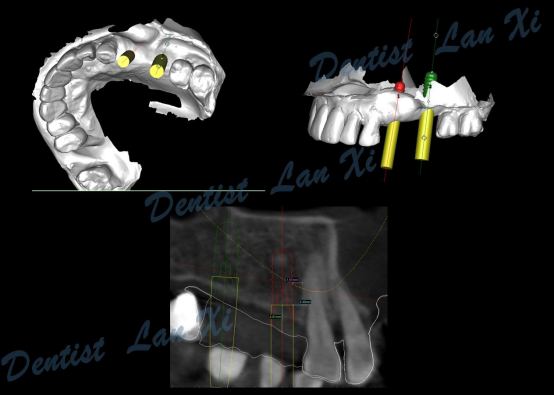

数字化种植导板是通过导板设计软件对CBCT、口扫等一系列数据的系统性分析,辅助口腔种植位点的设计,然后通过3D打印技术等途径进行导板生产,从而实现精准定位的种植手术装置。

简单来讲,数字化种植外科导板(简称导板),是将术前软件设计的种植方案,精确转移至患者口内的个性化手术辅助配件。

第三步:植入及导板设计